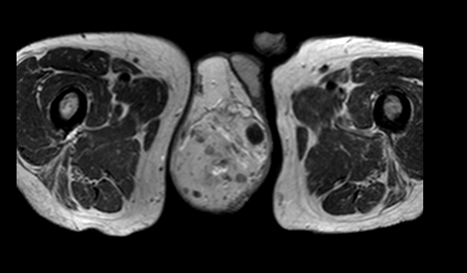

A 55-year-old male diagnosed with prostate cancer in 2010 and underwent radical prostatectomy followed by salvage radiation therapy to the prostatic fossa. He was found to have bone metastasis and since had been treated with hormonal therapy, enzalutamide, abiraterone, radium-223, and taxotere. In April 2016, the patients PSA was >1500 ng/dl. In August 2016, the patient,s was found to have bone marrow involvement with anemia (hemoglobin 6.1 g/dL) and thrombocytopenia (platelets 32x103/ul). In November 2016, the patient began complaining of scrotal pain. Physical examination demonstrated an enlarged scrotum with palpable mass and magnetic resonance imaging (MRI) scan revealed a right testicular hydrocele containing multiple enhancing nodules (Figure 1) (Figure 2) (Figure 3) (Figure 4). At last follow-up on November 10, 2016, the patient continued to have scrotal pain, and required transfusions for anemia and thrombocytopenia and is currently being treated with carboplatin and cabazitaxel.

Cursor on image to zoom/Click text to open image

Figure 2: STIR magnetic resonance imaging scan coronal view showing multiple cystic masses within the right testicle.